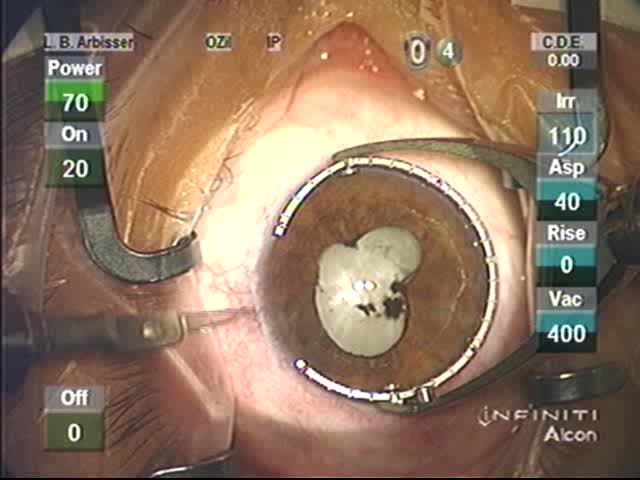

Morgagnian Cataract

Lisa Brothers Arbisser, MD